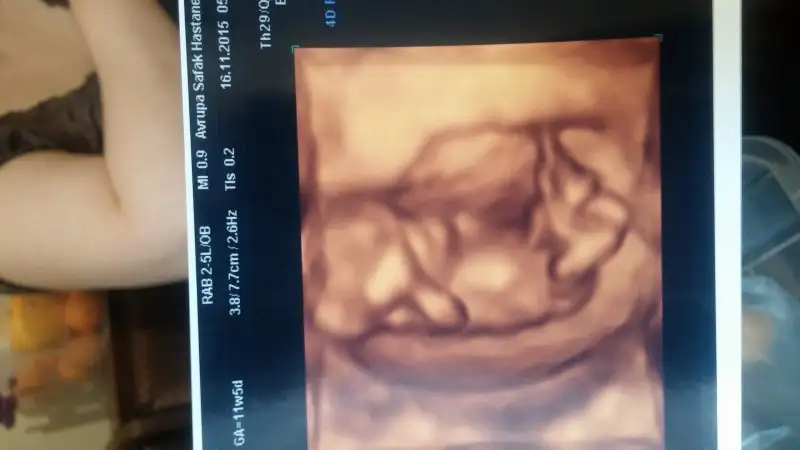

ay inşallah erkek tir. çok istiyorum bir oğlum olsun rabbim kalbimi biliyor. tabiki sağlıklı sıhhatli olsun diyorum ama yinede içime hep erkek doğuyo, rüyalarıma giriyor hep bir oğlan çocuğu emziriyorumcanım ultrason karındansa erkek, vajinal ise kız bebişin olma ihtimali yüksek. Allah gönlüne göre versin tatlım :)

Allah gönlüne göre versin tatlımay inşallah erkek tir. çok istiyorum bir oğlum olsun rabbim kalbimi biliyor. tabiki sağlıklı sıhhatli olsun diyorum ama yinede içime hep erkek doğuyo, rüyalarıma giriyor hep bir oğlan çocuğu emziriyorum

mrb canım ben ilk önce ulrason görüntülerini büyük sandım. o yüzden plasenta yönü yorumu yapmadım ama ikinci foto 7+3 günlükmüş. orda plasenta sağ altta görünüyor şayet ultrason karındansa kız, vajinal ise erkek olma ihtimali yüksek canım. allah gönlüne göre versin canım.Kızlar bana bidaha bakin persembe yine gidecem ama usg almadim en sin gittigimde Eki Görüntüle 1711090 Eki Görüntüle 1711088 Eki Görüntüle 1711088 Eki Görüntüle 1711089 Eki Görüntüle 1711090 Eki Görüntüle 1711089